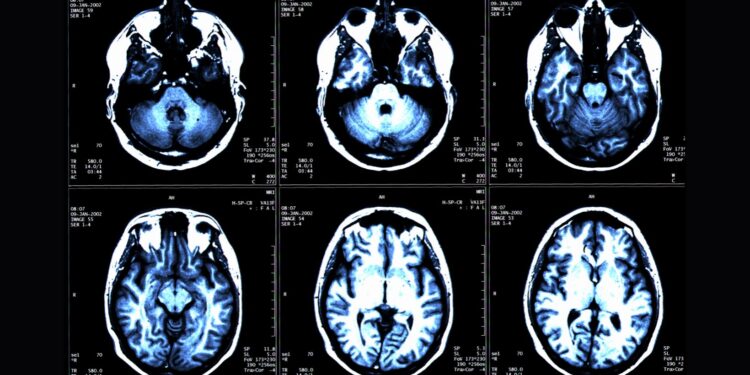

미국 워싱턴대 의대 사이러스 라지 박사팀은 25일 전신 MRI로 건강한 성인 1천100여명의 근육과 지방, 뇌 조직을 촬영하고, 총근육량과 내장지방, 피하지방, 뇌 나이 간 관계를 인공지능(AI)으로 분석한 결과 근육량이 많고 내장지방 대비 근육 비율이 낮으면 뇌 노화 속도가 느린 것으로 나타났다고 밝혔다.

연구팀은 이 연구에서 뇌의 구조적 MRI 영상의 부위별 부피를 기반으로 추정한 뇌 나이와 전신 MRI로 측정한 총근육량과 내장지방, 피하지방 사이의 연관성을 인공지능 알고리즘으로 분석했다.

이들은 4개 지역 거주자 1천164명(평균 나이 55.17세)을 대상으로 전신 MRI를 촬영하고 이를 지방과 체액, 근육 등이 다른 색으로 보이게 하는 기법과 결합해 총근육량과 내장지방 피하지방, 뇌 나이를 정량화했다.

그 결과 총근육량이 많을수록 실제 나이가 더 적고 뇌 MRI로 계산한 뇌 나이도 더 젊은 것으로 나타났다. 총근육량과 실제 나이 및 뇌 나이 간 상관계수(rp)는 각각 -0.2579와 -0.2497로 약한 연관성을 보였지만 통계적으로 유의미했다.